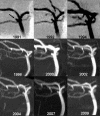

Results: Forty-five saccular aneurysms were detected in 38 patients from 36 families. Most were small (median diameter 3.5 mm) and in the anterior circulation (84%). Median age at diagnosis was 49 years. During cumulative imaging follow-up of 243 years, one de novo UIA was detected and increased in size from 2 to 4.4 mm over 144 months and two UIAs grew from 4.5 to 5.9 mm and 4.7 to 6.2 mm after 69 and 184 months, respectively. Seven patients did not have imaging follow-up. No change was detected in the remaining 28 patients. During cumulative clinical follow-up of 316 years, no aneurysm ruptured. Five patients died from unrelated causes and two were lost to follow-up after 8 and 120 months. Three patients underwent surgical clipping.